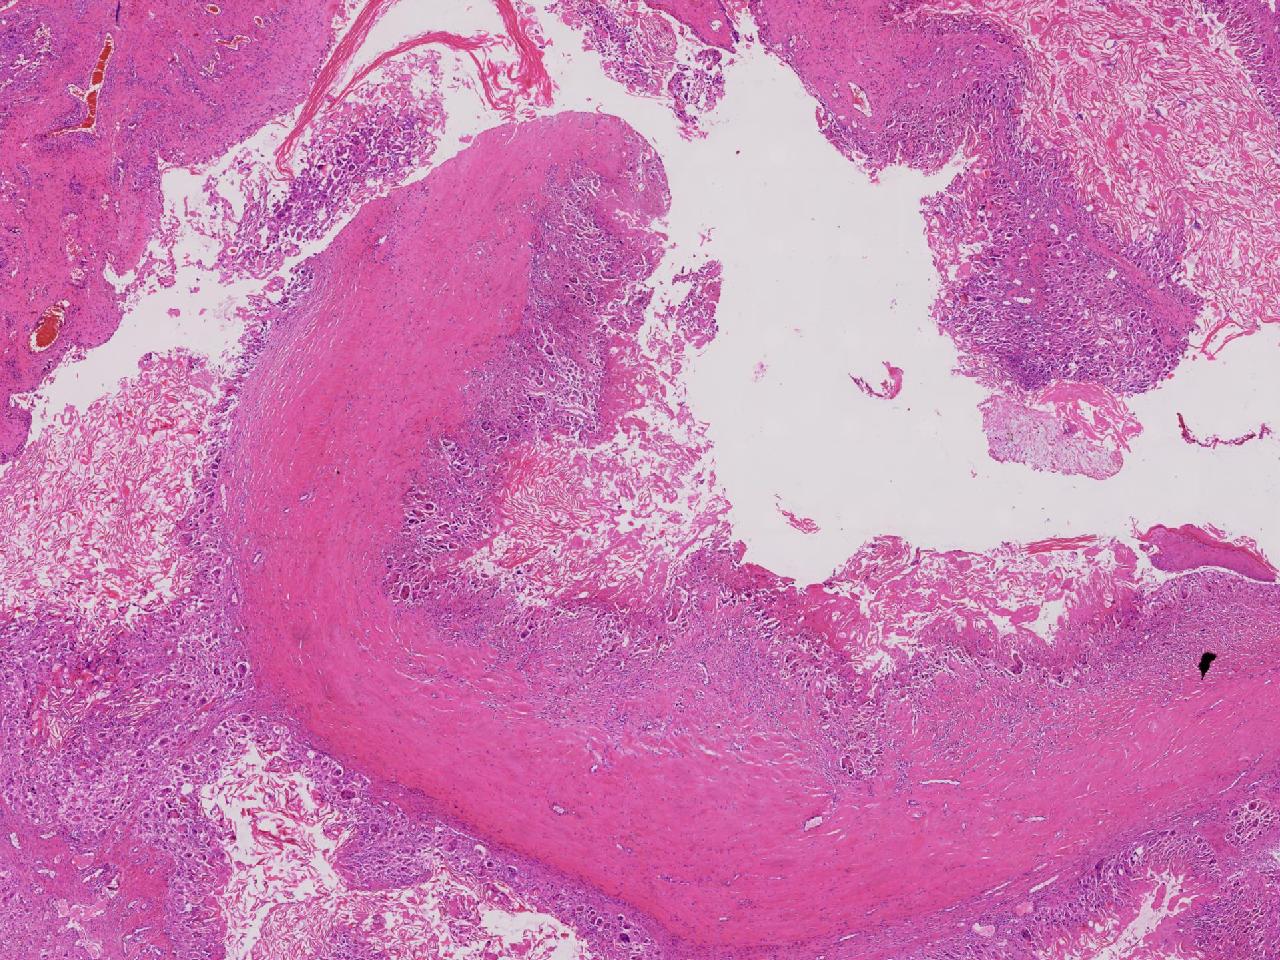

皮样/表皮样囊肿伴周边异物巨细胞反应?

右侧臀部皮下肿物10余年,渐增大,无破溃,无疼痛。

右侧臀部皮下肿物

囊性肿物一个,直径2.5厘米,肿物位于皮下。

异物肉芽肿性炎?

表皮样囊肿伴异物肉芽肿性炎。